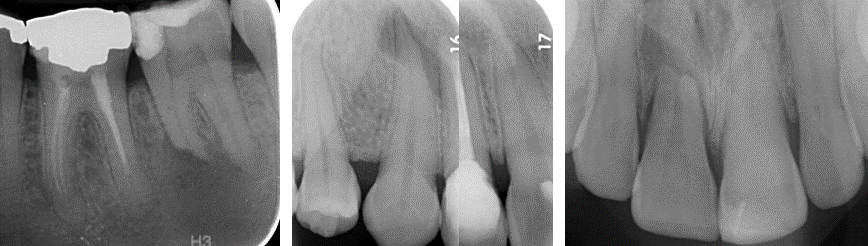

what has happened here

Trabecular pattern in area of resorption – healed, but still external surface resorption

Can be caused by

* Ectopic teeth – pressure from erupting tooth

* Pathological lesions - ameloblastomas

* idiopathic